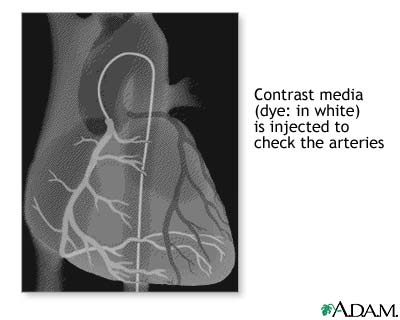

Coronary artery balloon angioplasty - series: Procedure, part 5

Once the catheter has been positioned at the coronary artery origin, contrast media is injected and a series of X-rays (film) are taken to check for any change in the arteries. Following this, the catheter is removed and the procedure is completed.